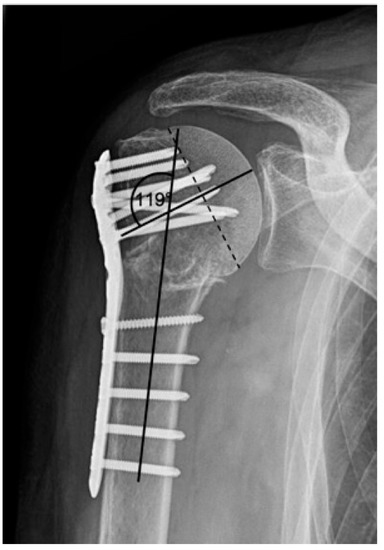

- primary unsuccessful surgical reduction (>5° head–shaft displacement, cranialization of the greater tuberosity of >5 mm and valgus head–shaft alignment >150° or <110° head shaft angle according to Schnetzke et al., 2016) [20].

| Complication Type | Exemplary Images by X-rays or Pattern Images | Definition |

|---|---|---|

| 4 | ![]() | Complication Type 4a is based on the presence of AVN of the humeral head without concomitant destruction of the glenoid articular surface due to an associated screw cutout through the humeral head cortex. |

| 4b | ![]() | Complication Type 4b is also based on the presence of an AVN of the humeral head combined with a destruction of the glenoid articular surface due to the associated screw cutout through the humeral head cortex. |